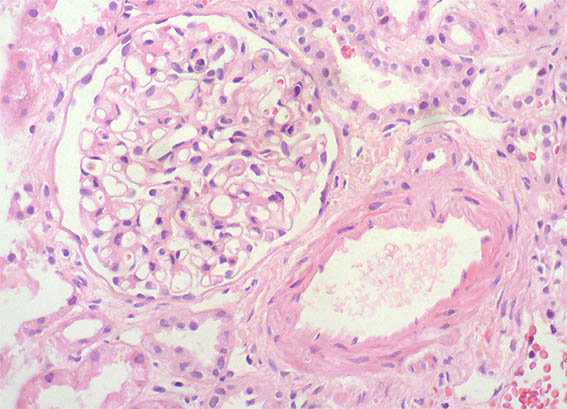

A 25-year-old woman with no relevant history is evaluated for presenting 3 months of evolution of constitutional symptoms, disseminated skin lesions with vasculitis-like appearance, polyarthritis affecting small and medium joints, anemia, acute phase reactants elevation, lymphopenia, hypocomplementemia C3 and C4, uroanalysis with active sediment and subnephrotic proteinuria: 1.8 g/24h; Cr; 1.1 mg/dL, BUN: 18 mg/dL. ANAs and anti-DNA positive at high titers, anti-RNP positive, VDRL falsely positive. Anticardiolipin and lupus anticoagulant: negative, other markers for APS: Negative.

See the images of the renal biopsy.

Figure 1. H&E, X100.